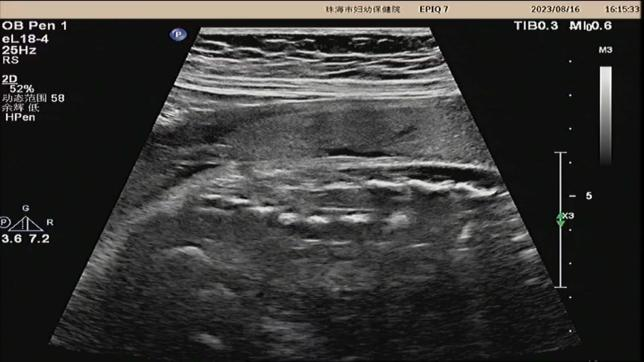

孕晚期,医生拍下我存在的证据(孕 31W+1 天;超声图)

我比较小,喜欢和小朋友玩「藏猫猫」的游戏,经常躲在他们从枕部到骶尾部间的任何地方,我最喜欢的是腰骶部。当然,秉着有福同享的理念,我时常会带上我最好的兄弟脊椎裂和脊髓栓系。